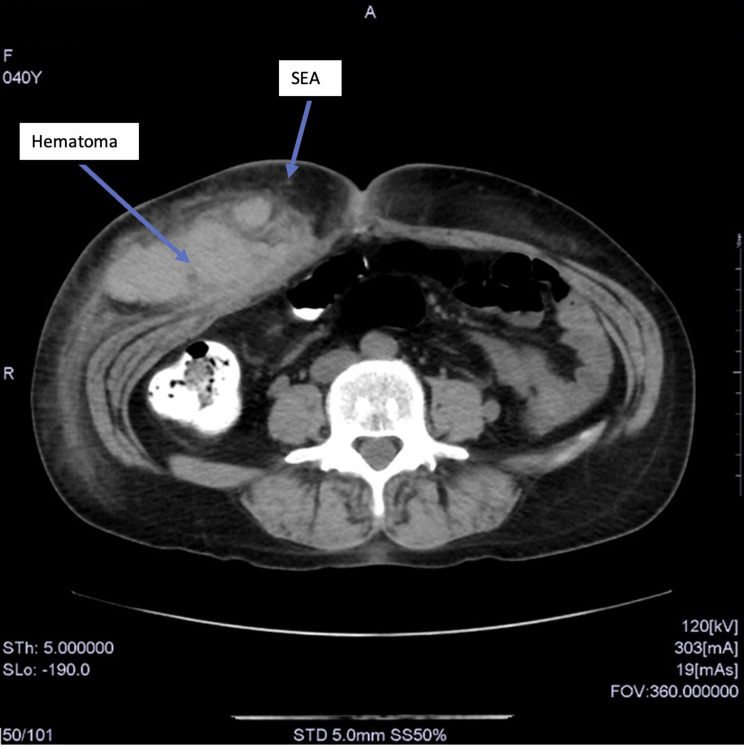

Case presentation: A 40-year-old female underwent bilateral ultrasound-guided rectus sheath block and transversus abdominis block following laparoscopic cholecystectomy. After the operation, a large, painful hematoma was identified with a volume estimated at 430 mL. Investigation of the bleeding site by CT scan showed that the hematoma was subcutaneous and in an area with multiple venous and arterial branches. Identification of the responsible vessel appeared difficult; however, on discussion with the radiologist, bleeding from a cutaneous (or deeper) vessel from the block or surgical (trocar or needle) injury was included in the different diagnosis. The superficial epigastric artery was considered the most probable source because it was the closest to the hematoma.